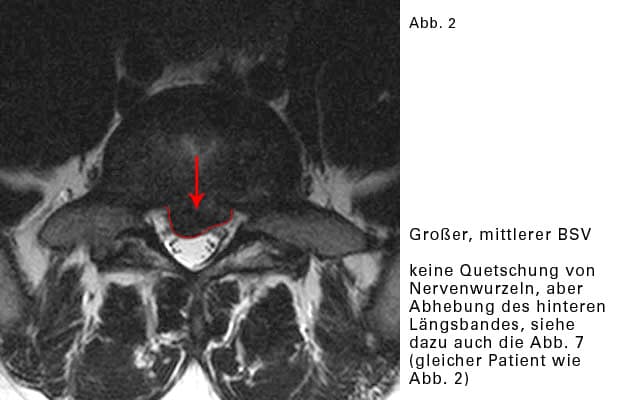

Mittlerer Bandscheibenvorfall:

Der Riss des Faserringes liegt in der Mitte. Der Vorfall rutscht in den mittleren Bereich des Wirbelkanales, wo relativ viel Raum ist. Nervenwurzeln werden hier nur gequetscht, wenn der Vorfall sehr groß ist.

Reizung des hinteren Längsbandes

Ein kräftiges Band überzieht die hinteren Flächen der Wirbelkörper und die Bandscheiben. Es begrenzt die bauchwärts gelegene Wand des Wirbelkanales (sh Bild).

Das hintere Längsband wird durch einen BSV „ausgebeult“. In jedem Band des Körpers befinden sich Nervenrezeptoren. Sie registrieren Spannungen und Schmerzen und leiten ihre Messergebnisse weiter an das Rückenmark, an das Gehirn. Wird das hintere Längsband „ausgebeult“ und durch Bücken zunehmend gedehnt, dann „funken“ die Nervenrezeptoren: es schmerzt.